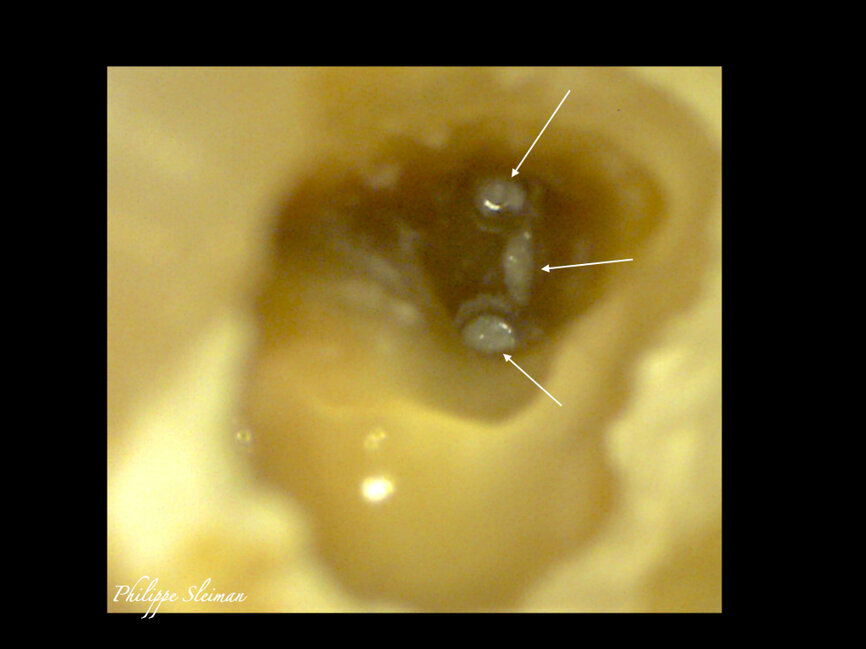

The patient was referred for a root canal therapy of his maxillary molar. Upon creating the access cavity under a clinical microscope, we could see that the entry to the second mesial canal was at a distance from the entrance to the first (Fig. 5). Figure 6 shows the proximity of the second mesiobuccal canal to the palatal canal. Increasingly, second mesial canals are being treated in the maxillary second molar owing to the use of the microscope, ultrasonic instruments and irrigation and of course owing to the clinical knowledge regarding the use of these and owing to the use of CBCT imaging sometimes.